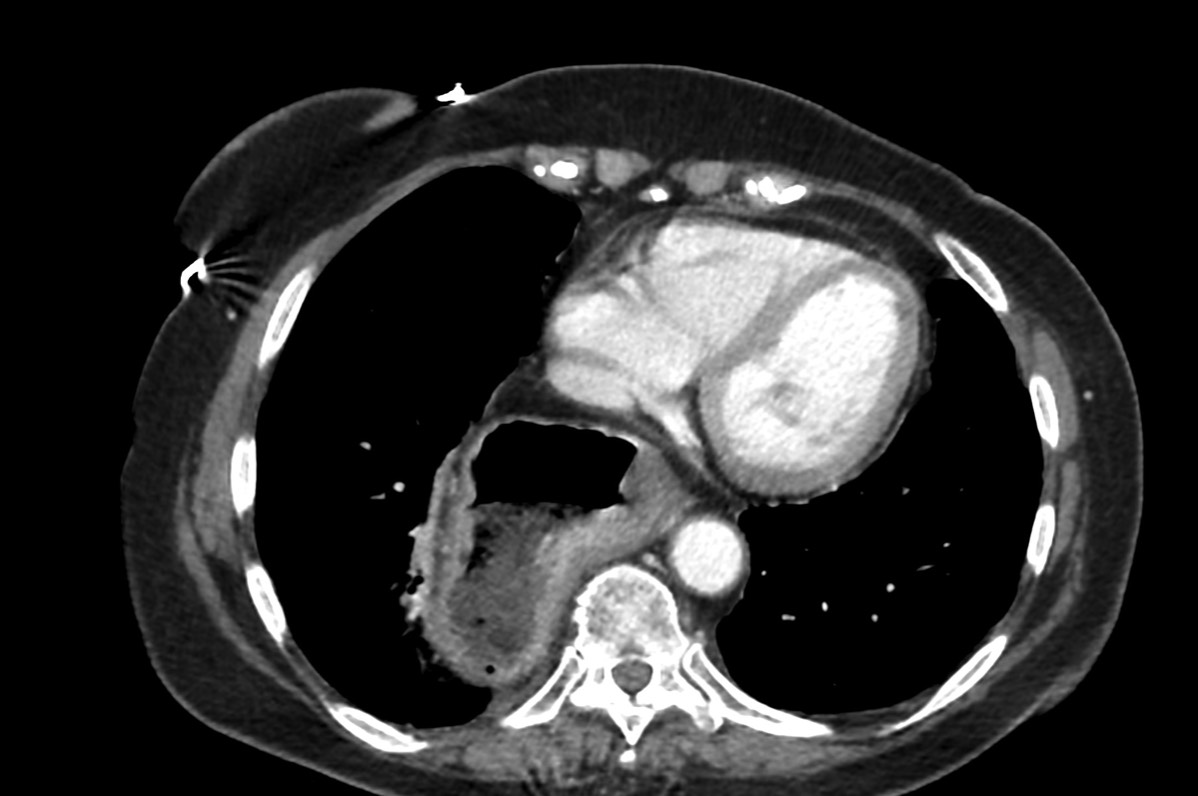

3) Αξονική τομογραφία ύστερα από κατάποση γαστρορραφινης,εξεταση που μας επιτρέπει να διαγιγνώσκουμε τον τύπο της διαφραγματοκηλης

Εικονες απο αξονικη τομογραφια και ενδοσκοπηση